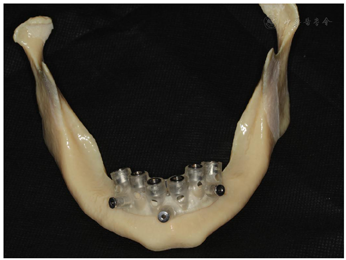

辅助检查:3D打印上下颌骨模型,可见上颌缺牙区域剩余牙槽嵴菲薄,颧骨厚度不佳,下颌颏孔靠近牙槽嵴顶,牙槽嵴顶向内吸收,咬合空间尚可(图7)。

将CBCT的DICOM数据转为STL格式后获得数据模型,找到下颌切牙管前端A,颏孔C,和A与C曲线的中点B,在A点和B点设置两颗固位钉,联合颏孔C形成下颌切牙管指示定位导板(图11,图12,图13,图14,图15)。